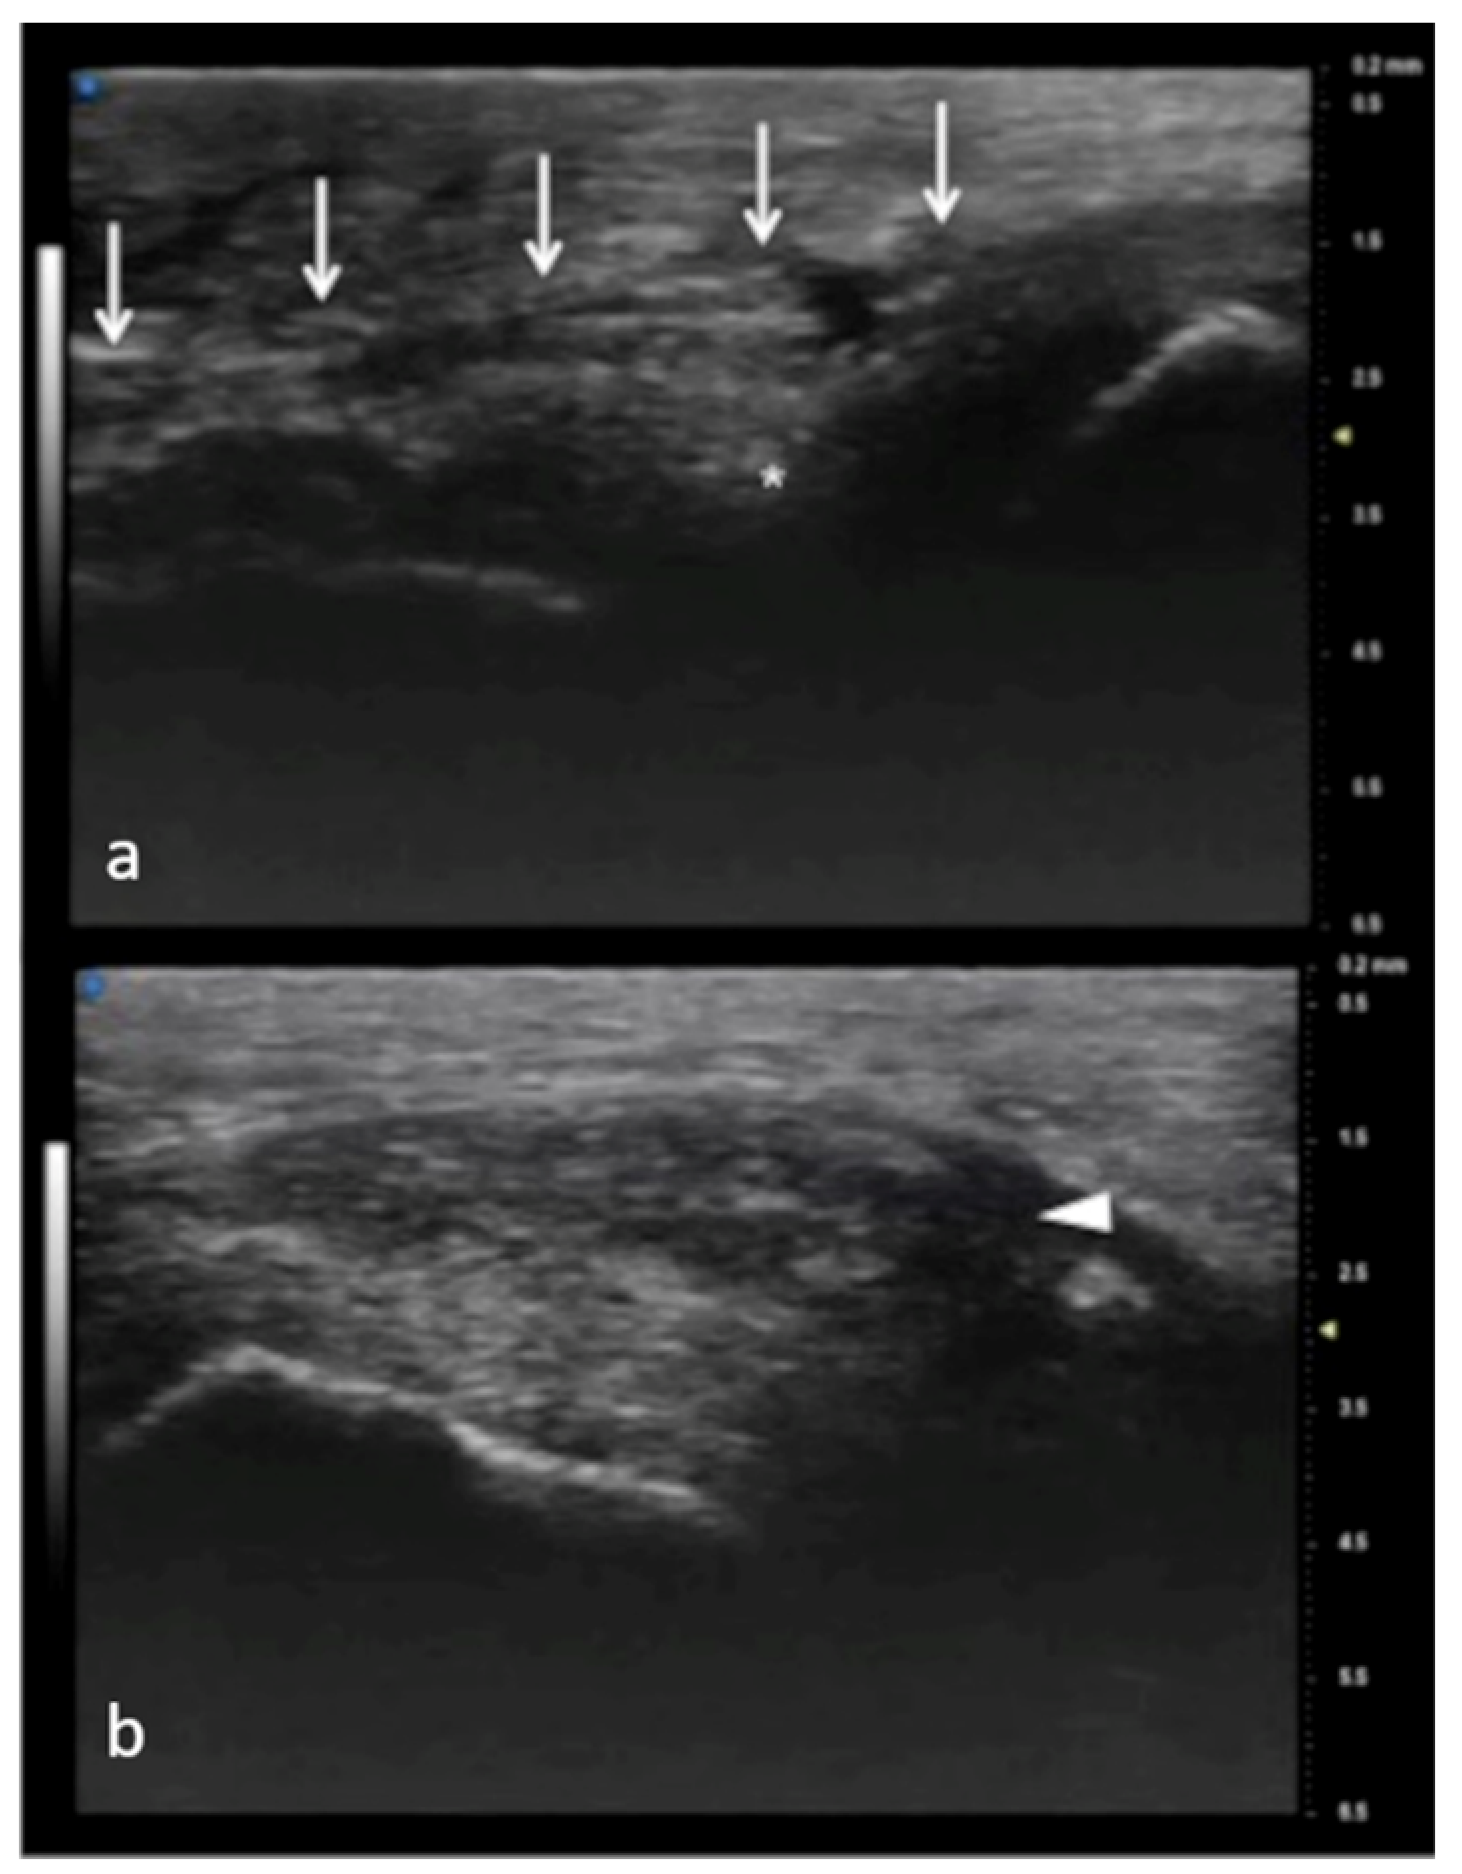

Collateral ligaments of interphalangeal joints: comparison between 50 MHz probes in (a) and 15 MHz CUS (arrowheads) in (b). In (a), UHFUS gives a more detailed and magnified representation of both deep (white arrows) and superficial (white arrowheads) components of the ligament.